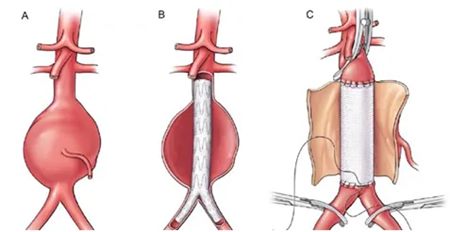

目前主要有两种手术方式:

微创腔内修复术(EVAR)

经大腿根部股动脉穿刺,导入覆膜支架,在瘤腔内重建血流通道;创伤小、恢复快,但对患者血管解剖条件有一定要求。

传统开放手术

开腹切除瘤体,置换为人造血管;

创伤较大,但适用广泛、效果持久。

▲ 腹主动脉瘤“覆膜支架腔内隔绝术”与“人工血管置换术”